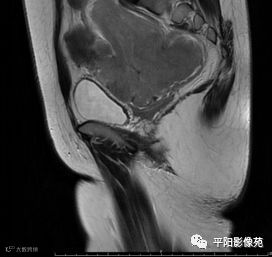

MRI表现

T2矢状位

(宫腔内见金属节育环伪影)宫颈区见不规则形等T1稍长T2信号软组织肿块,DWI序列呈明显高信号,大小约为3.87cmX2.64cm,双侧宫颈基质低信号环连续性中断,病灶向子宫右后上方生长,周围脂肪间隙模糊,增强扫描明显强化,强化程度低于子宫及宫颈实质;子宫后方、子宫直肠间隙见不规则形长T1长T2信号软组织肿块,DWI序列呈高信号,大小约10.12cmX4.82cmX10.29cm,病灶呈分叶状,向下方生长与宫颈分界不清,与直肠分界尚清,增强扫描明显不均匀强化。